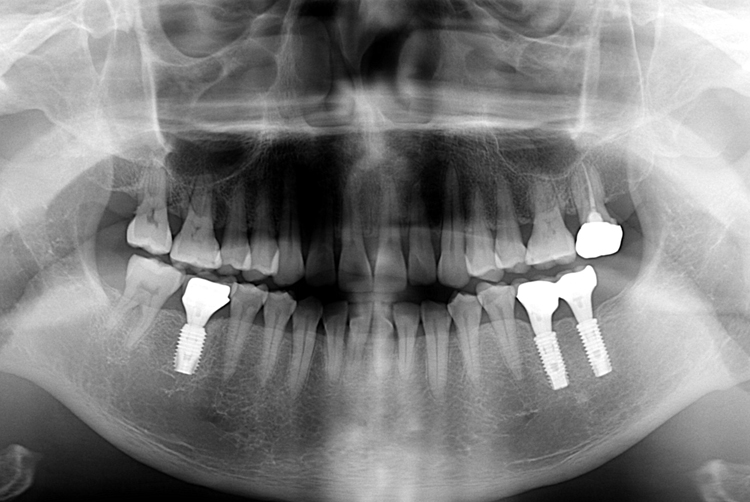

[임플란트] 어금니 임플란트

치료후 : 2018-09-05

세종치과는 많은 환자와 다양한 케이스를 바탕으로

항상 편안한 임플란트 수술을 제공하고자 노력하고,

오래동안 튼튼히 쓸 수 있는 임플란트 수술을 가장 큰 목표로 삼고 있습니다.